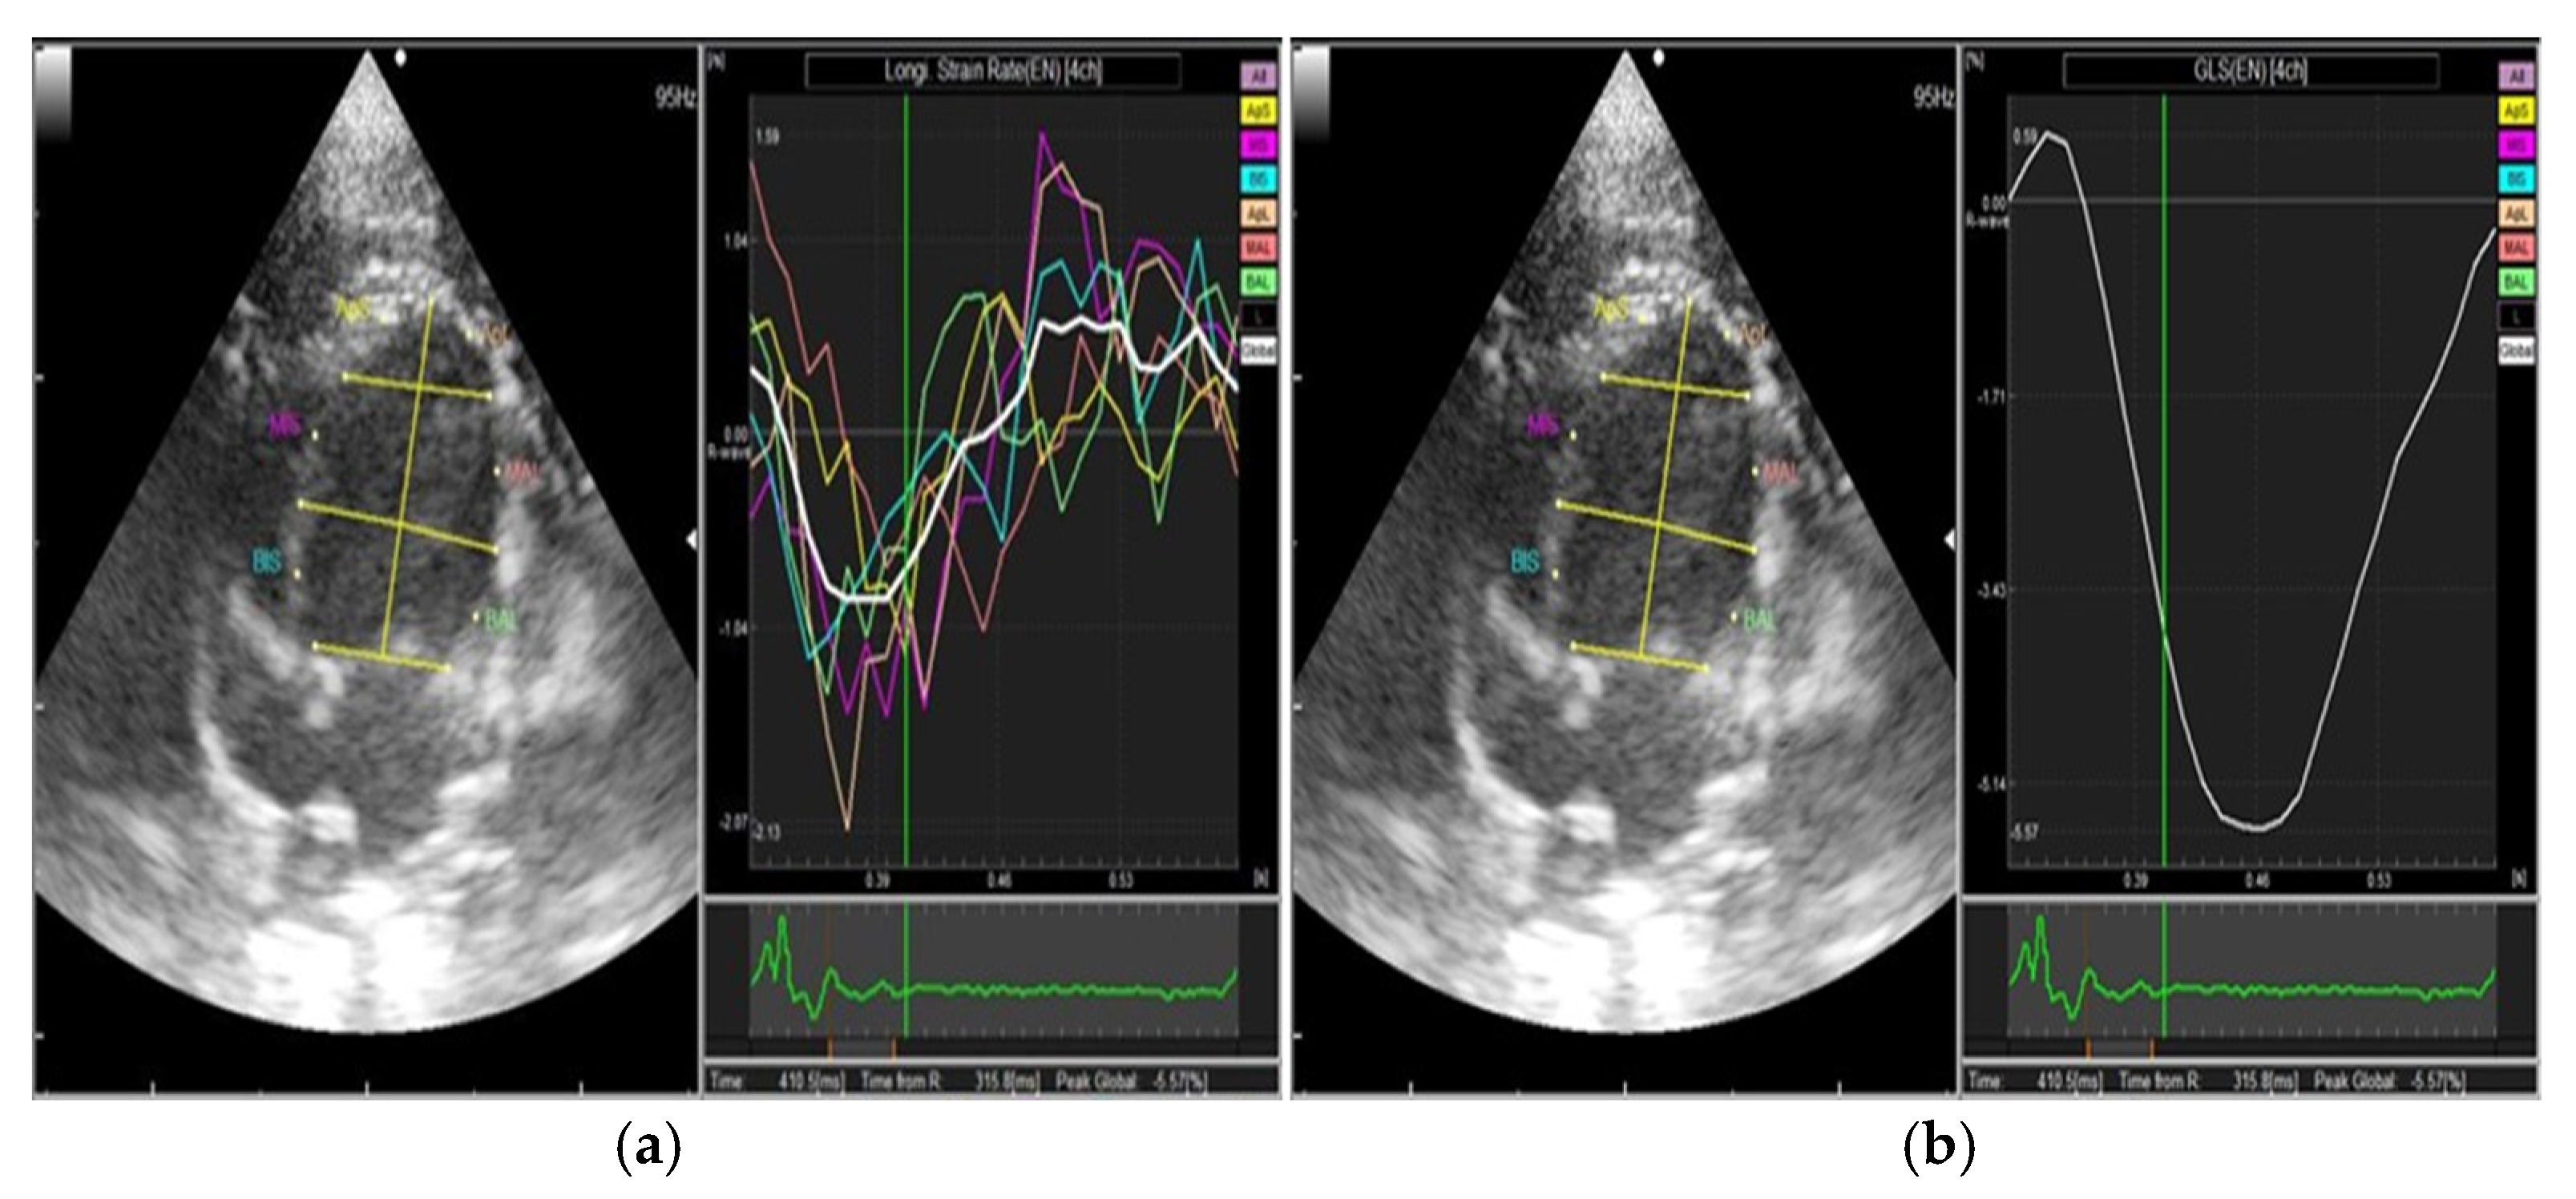

2.3. Two-Dimensional Speckle Tracking Echocardiography (2DSTE)

3.2. Two-Dimensional Speckle Tracking Echocardiography